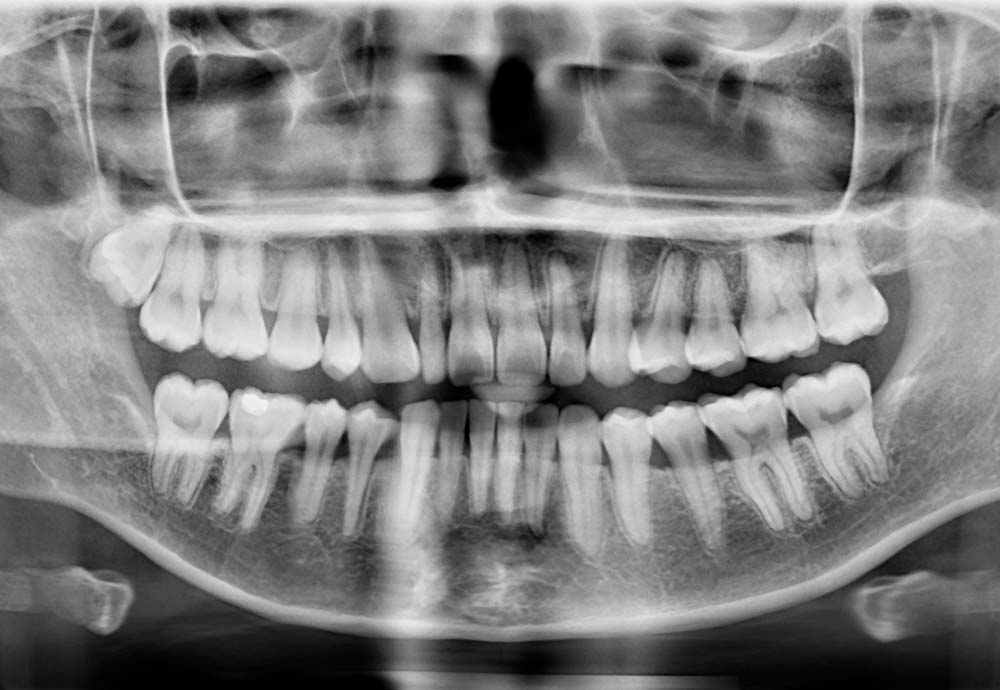

Wisdom teeth may need to be removed if they are impacted, causing pain, swelling, infection, or damage to nearby teeth.

Other reasons include preventing future dental problems such as decay, gum disease, cysts, or crowding of your existing teeth.

Wisdom tooth removal is generally safe, but like any surgical procedure, there are some risks such as nerve irritation and infection.

In rare cases, lower wisdom teeth may be close to a nerve, which could cause temporary numbness. To improve safety, we use Piezo-assisted surgery and laser disinfection, which help protect nearby tissues and support faster healing.